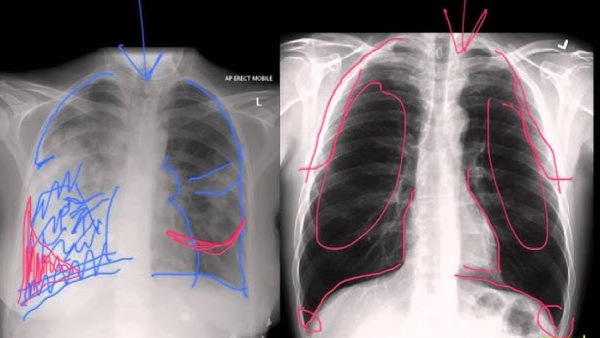

చలికాలంలో సాధారణంగానే పలు వ్యాధుల బారిన పడుతుంటాం. అందులో ముఖ్యమైనది న్యూమోనియా. ఇది ఒక రకమైన ఇన్ఫెక్షన్. ఇది బ్యాక్టీరియా, శిలింద్రాలు, వైరస్ల వల్ల వస్తుంది. ఈ వ్యాధి కారణంగా శ్వాసకోశ సంబంధిత సమస్యలు, చాతి నొప్పి వంటి సమస్యలు వస్తాయి. పిల్లలు, వృద్ధులను ఈ వ్యాధి అమితంగా ప్రభావితం చేస్తుంది. ఒక్కోసారి ఇది ప్రాణాంతకంగా కూడా మారుతుంది.

ఈ న్యూమోనియా ఊపిరితిత్తులను వాపుకు గురి చేస్తాయి. అలాగే ఊపిరి తిత్తుల్లో శ్లేష్మం, ద్రవం నిండిపోయేలా చేస్తుంది. ఇది శ్వాసను తీసుకోవడాన్ని నిలిపివేసి శరీరంలో ఆక్సిజన్ శాతాన్ని తగ్గిస్తుంది. క్రమంగా మనిషి చనిపోయేంత వరకు తీసుకెళ్తుంది. దీనిని ముందుగానే గుర్తించి చికిత్స తీసుకోకపోతే వ్యక్తి వయస్సు, ఆరోగ్య పరిస్థితిని బట్టి ప్రమాదకరంగా మారుతుంది.